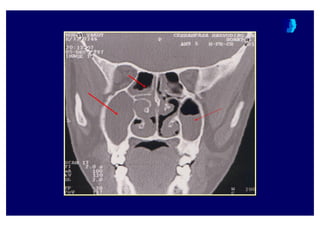

Water’s grafisiWaterWater’’ss grafisigrafisi

Coronal BTCoronalCoronal BTBT

BT ne zaman istenmelidir ?BT ne zaman istenmelidir ?BT ne zaman istenmelidir ?

• Yo4un bir tedaviye cevap al namad 4 taktirde

KBB uzman taraf ndan

• Komplikasyon riski ta( yan olgularda

• Pre-operative de4erlendirme